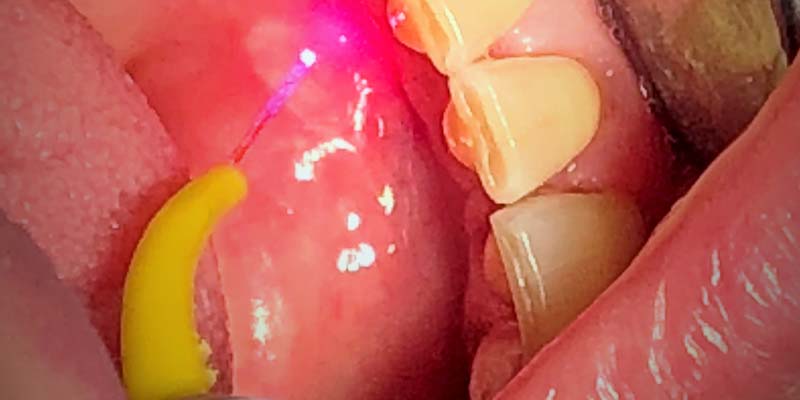

Si distinguono clinicamente una forma “ Minor” , caratterizzata da lesioni di piccola dimensione , in genere non superiori ad un cm che si localizzano generalmente a livello della mucosa orale non cheratinizzata, (vestibolo orale, ventre linguale, pavimento orale, mucosa labiale). La guarigione è spontanea e avviene con restituito ad integrum dei tessuti in un paio di settimane dall’esordio, ed una forma “ Major”, in cui le ulcere hanno un diametro che può raggiungere e superare il centimetro, guariscono in tempi più lunghi rispetto alle afte minor e spesso lasciano una cicatrice, la mucosa interessata è quella del palato o del dorso linguale. Come già accennato le afte vanno incontro ad una guarigione spontanea nel giro di sette dieci giorni e il trattamento, ad oggi , è indirizzato al solo scopo di ridurre la sintomatologia e abbreviare il decorso delle lesioni; si avvale classicamente dell’utilizzo di preparati per uso topico a base di corticosteroidi, di aloe, di sodio jaluronato e aminoacidi o di antisettici (per evitare la sovrainfezione della mucosa lesionata). Un’arma in più è rappresentata dall’uso del laser a diodi , che ha dimostrato di ottenere ottimi risultati , grazie alla sua capacità di sterilizzazione dei tessuti infetti e di stimolazione del processo di guarigione, tale cherisulta essere, attualmente, lo strumento ideale per la terapia di queste dolorosissime lesioni, che, se trattate nel giro di 24 ore o poco più, hanno una rapidissima remissione ed un’immediata riduzione della sintomatologia dolorosa.